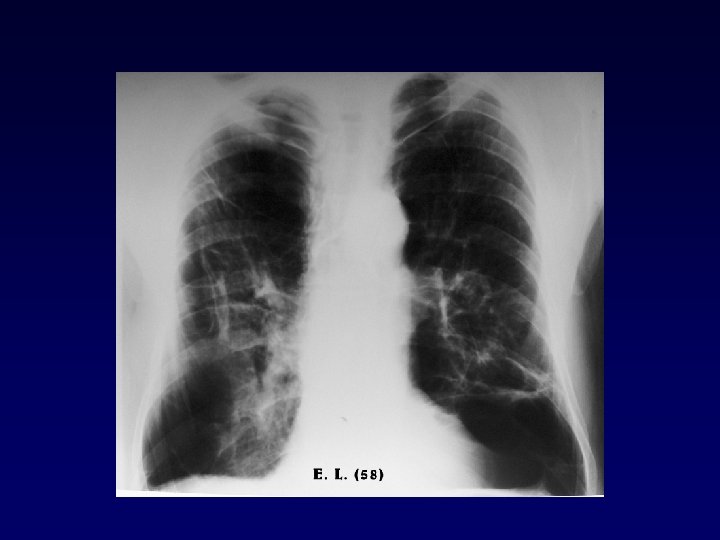

COPD emphysema bronchitis „pink puffer” „blue bloater”

Characteristics of phenotypes bronchitis Dynamic lung volumes decreased emphysema decreased ( FEV 1 , FEV 1/FVC) Static lung volumes TLC RV Diffusion capacity normal or mild increase moderate increased increasd normal or mild decreased Blood gas hypoxaemia, hypercapnia hypoxaemia in end-stage exercise hypoxaemia: no change, improves or deteriorates hypoxaemia deteriorates Cor pulmonale frequent rare

Respiratory insufficiency in COPD acute exacerbation pink puffer partial (hypoxaemic/transfer failure) blue bloater global (pump-, ventilatory failure)